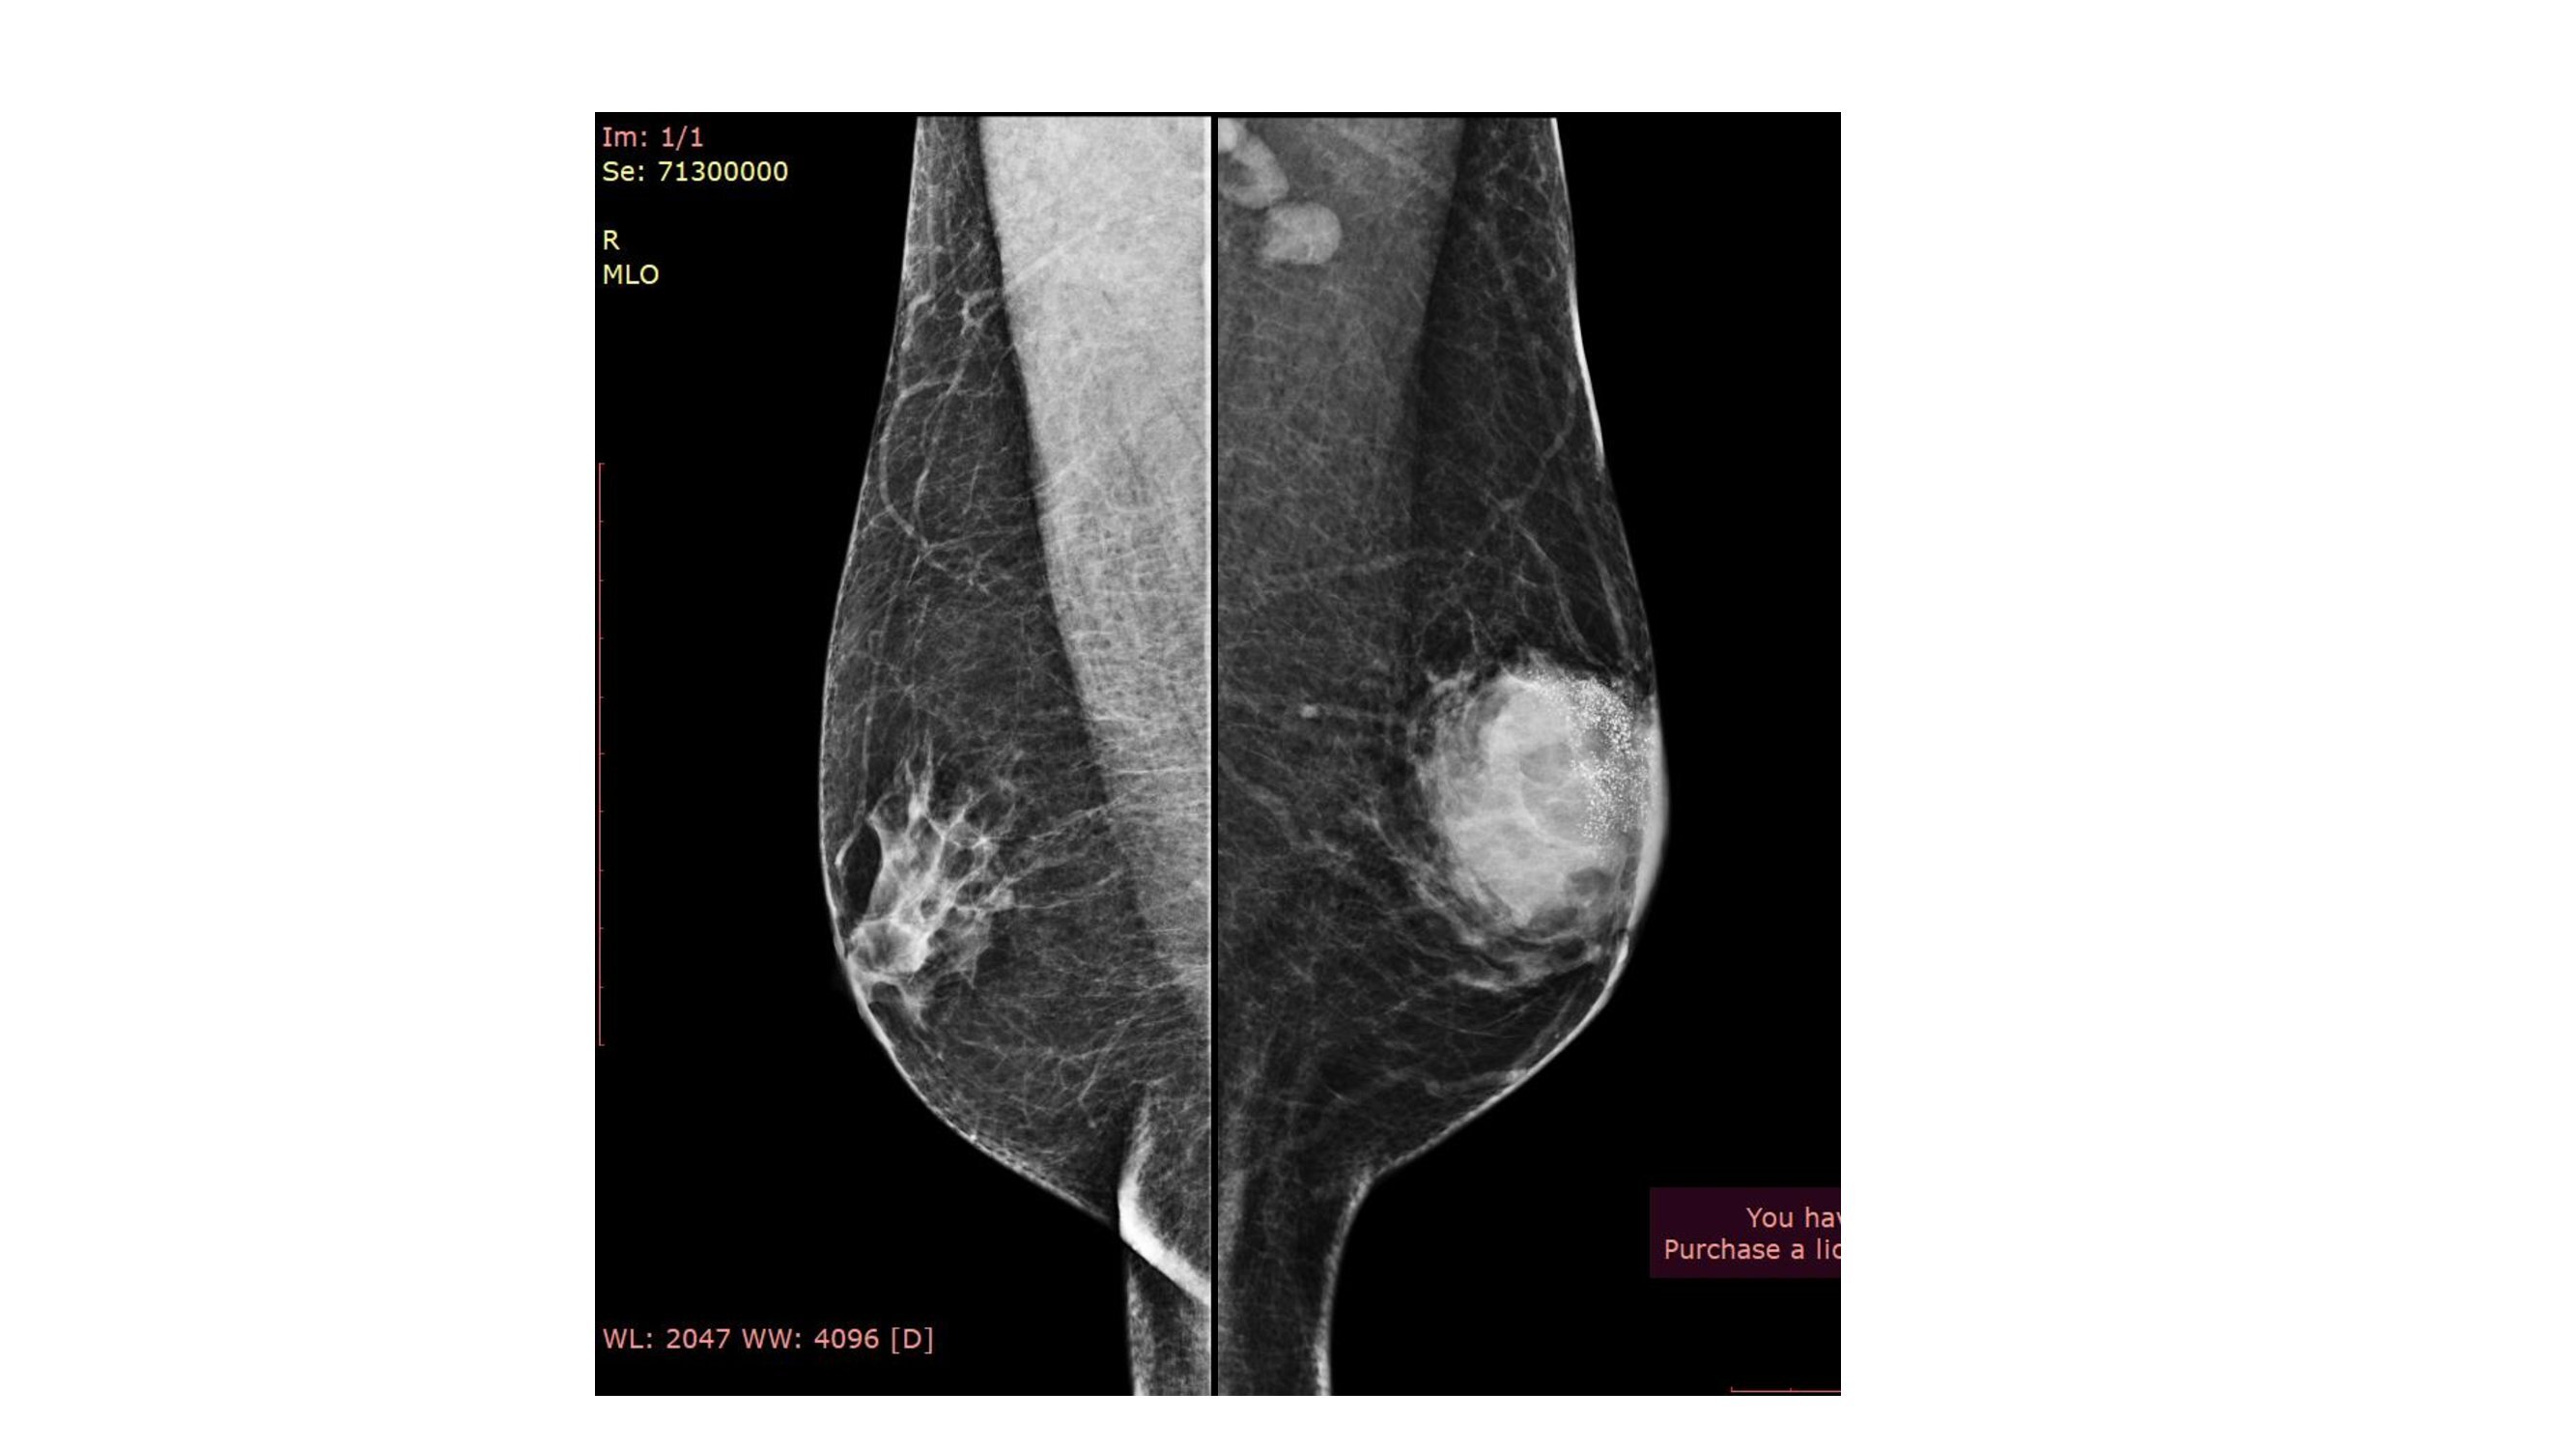

A circumscribed high density lesion ( size 4.5x5.5x6cm) is noted in the upper outer quadrant extending to the retroareolar region . On tomosynthesis, irregular margins were seen. There are fine pleomorphic microcalcifications in the lesion. The lesion is abutting the overlying skin. The skin is thickened and the nipple is retracted. The left axilla shows 2-3 lymph nodes with thickened cortex. On USG the mass was iso to hypechoic with irregular circumscribed margins with increased vascularity.There are mixed posterior features. Microcalcifications were seen in the upper outer region of the mass. BIRADS 5 was assigned for the lesion and USG guided biopsy was recommended. USG guided FNAC from the left axillary node showed only reactive lymphoid hyperplasia. USG guided core biopsy showed Invasive breast cancer NST, Nottingham Grade II. Immunohistochemistry report is awaited.